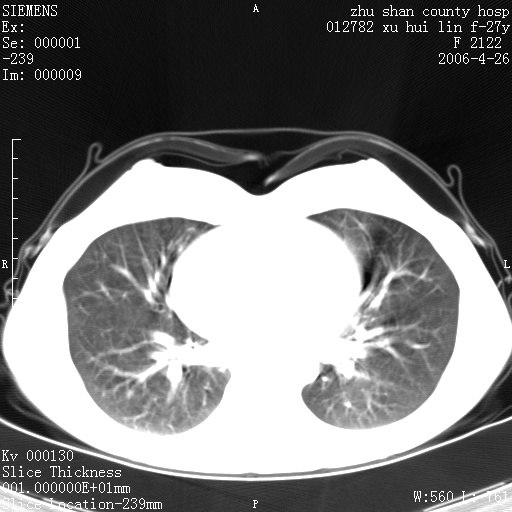

女性 病人 27岁!本院职工家属,五月前因感冒透视发现病变,ct示:左肺下叶背段感染性病变。经过半月规范抗生素治疗后复查病变无明显变化,后行四月规范抗痨治疗,复查无明显变化,后复查无效!请大家帮忙看看!

右肺下叶背段见片状高密度区,边界不清,密度不均,无钙化及空洞影,背段支气管通畅。所见层面肺门及纵隔内未见明显肿大淋巴结影。

女性 病人 27岁!本院职工家属,五月前因感冒透视发现病变,ct示:左肺下叶背段感染性病变。经过半月规范抗生素治疗后复查病变无明显变化,后行四月规范抗痨治疗,复查无明显变化,后复查无效!

诊断:首先还是考虑为慢性炎症。

结核虽然好发于下叶背段,但周围无明显卫星灶,化验结果怎样?